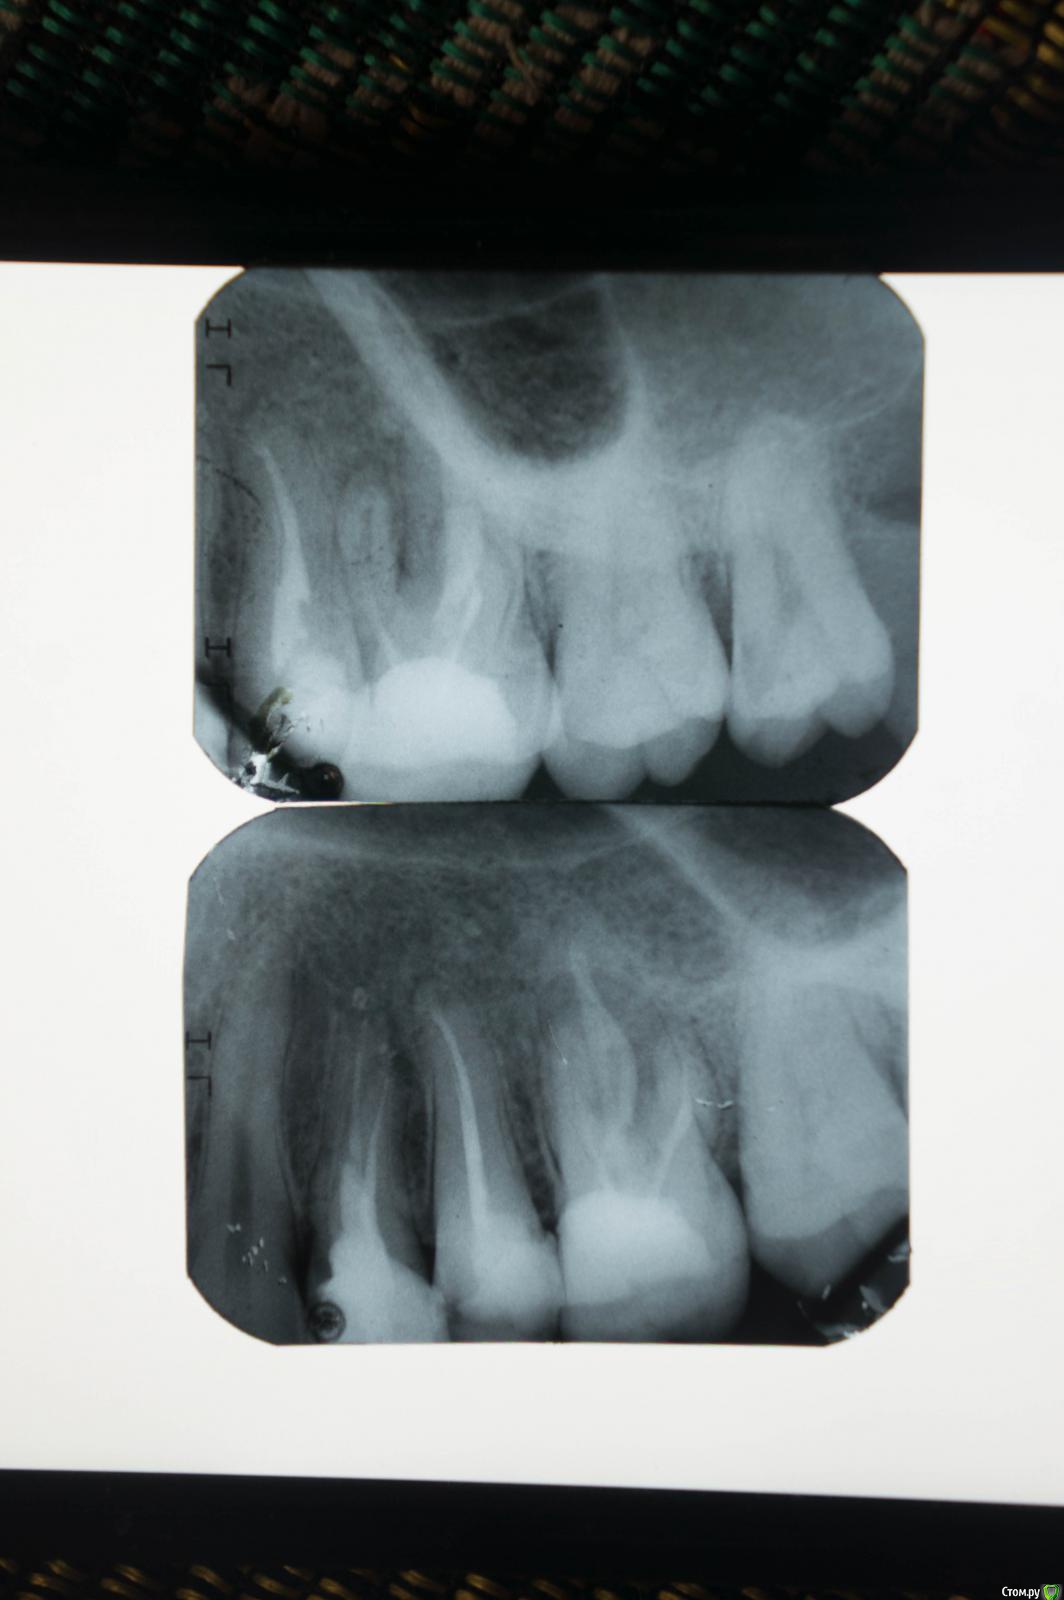

hectata Опубликовано 2 августа, 2016 Поделиться Опубликовано 2 августа, 2016 Добрый день! Буду признателен за совет. Около 4 месяцев назад над верхней правой 6-кой (зуб уже леченый, нервы удалены) появился свищ, из которого тёк гной. Обратился в стоматологию, сделали снимок и стоматолог-терапевт сказала, что на снимке виден перелом корня зуба, зуб нужно будет удалить, но пока нет острой боли, можно этого не делать и ходить со свищом. Я последовал совету врача и не стал пока удалять зуб.Сверху 1-ый снимок, снизу - 2-ойЧерез 3 месяца свищ закрылся, но появилось болезненное уплотнение на щеке выше 6-ки, стал появляться отек. Срочно обратился в стоматологию и попал к другому стоматологу-терапевту. Она снова направила меня на снимок, сказав, что на том снимке, который у меня имеется, перелома корня зуба не видно. На новом снимке перелома тоже не оказалось. Врач сказала, что проблема связана, скорее всего, с тем, что в зубе не запломбирован 4-й канал. Она настоятельно рекомендовала мне зуб сохранить, но сама лечить его не стала, мотивировав это отсутствием необходимых инструментов, а направила к знакомому эндодонту (озвучив примерную стоимость лечения – 30000 руб.). Также она назначила мне антибиотики, чтобы снять воспаление на щеке.Дело происходило в обычной городской стоматологической поликлинике. Имея на руках столь противоречивые мнения двух врачей, я решил обратиться в платное отделение этой же поликлиники (там работают другие врачи). В платном отделении врач, изучив оба снимка, согласилась с тем, что перелома корня зуба нет и что нужно искать и пломбировать 4-й канал, чтобы сохранить зуб. Врач предложила такой вариант: она вскроет зуб, заложит в него лекарство и попытается найти 4-й канал, а если у нее не выйдет, то направит к эндодонту (которого у них в поликлинике нет). Еще она сказала, что в случае удачного лечения, на зуб нужно будет поставить коронку.Подскажите, пожалуйста:Насколько реально сохранить эту 6-ку (смущает, что первый врач рекомендовал удаление)? Стоит ли сразу обращаться к эндодонту или можно лечить зуб у обычного стоматолога-терапевта?P.S. Пропил назначенный мне антибиотик, отёк и болезненные ощущения прошли всего на неделю, а теперь постепенно возвращаются обратно. Я ближайшие 2 недели в отпуске и обратиться к стоматологу возможности нет. Можно ли повторить курс Амоксиклава, если станет совсем невмоготу, или нужно пить другой антибиотик? Ссылка на комментарий

4ebstom Опубликовано 3 августа, 2016 Поделиться Опубликовано 3 августа, 2016 Перелома не видно. Перелечивание каналов и протезирование-вот что может спасти зуб... Ссылка на комментарий